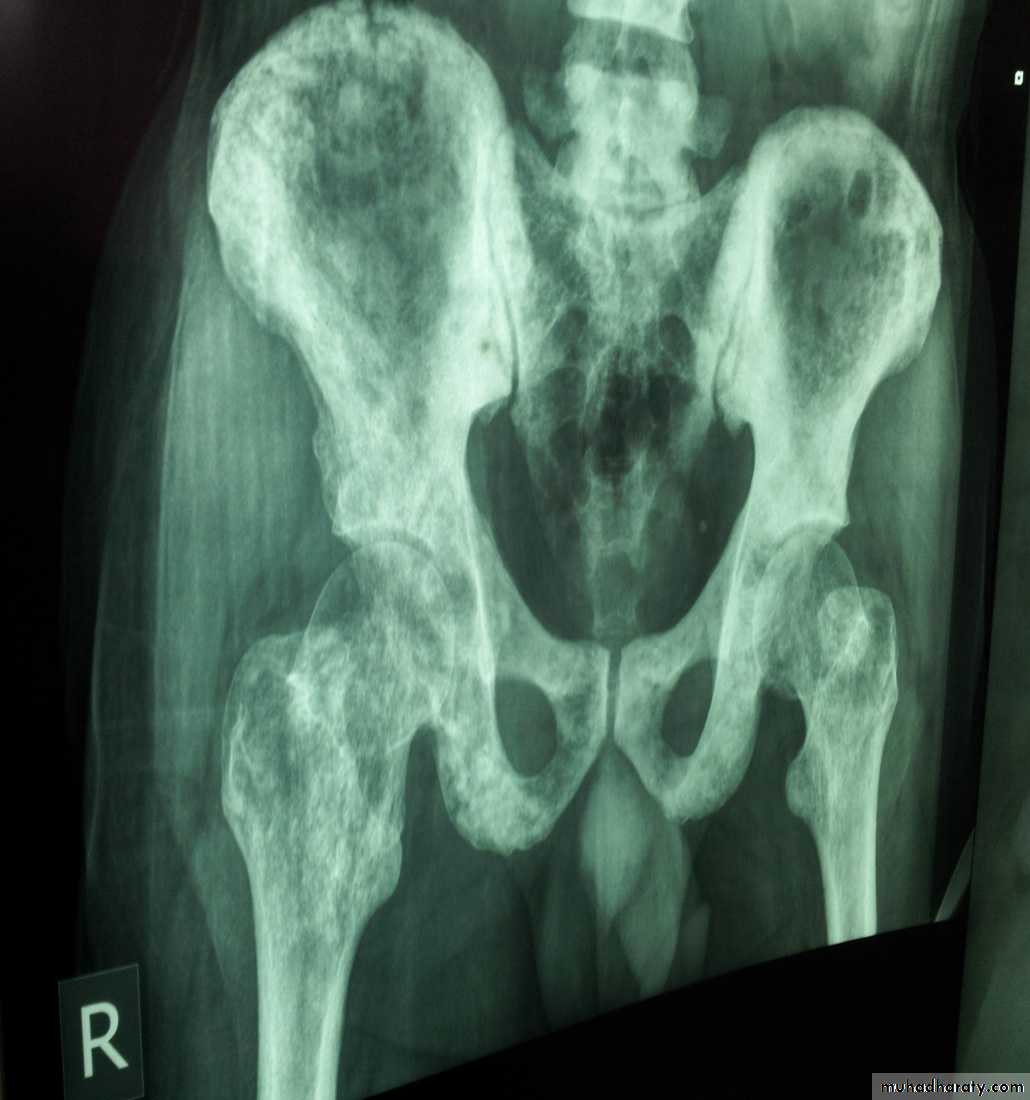

Blood spread : Bones, liver , lungsClinical features

X-Ray of bones + Isotope Bone scan